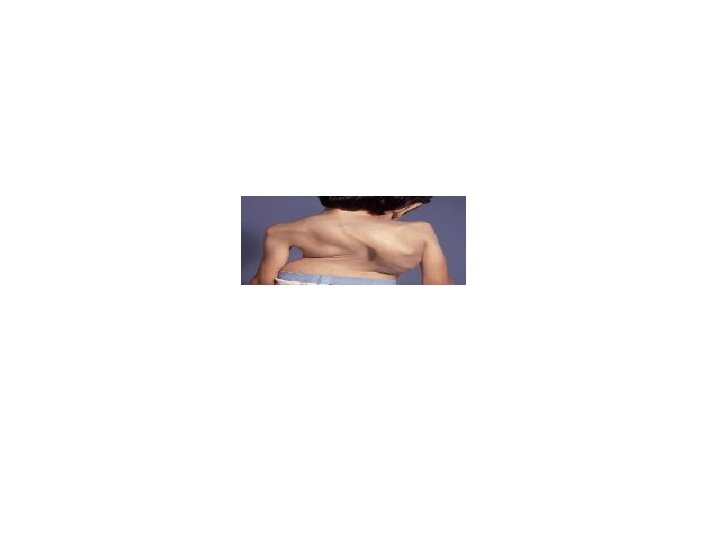

HANDS § Cyanosis § Clubbing---ca. bronchus ---TB ---empyema ---abcess ---fibrosing alveolitis ---bronchiectasis § Wasting of small muscles of hand ---pancoast tumour

EXAMINATION OF THE CHEST Inspection § A-P diameter --pectus excavatum---funnel chest --pectus carinatum---pigeon chest § kyphoscoliosis § respiratory movements---resp. rate-{14 -18/min} i: e –hyperventillation—DKA, PE ---hypoventillation—type 2 resp. failure